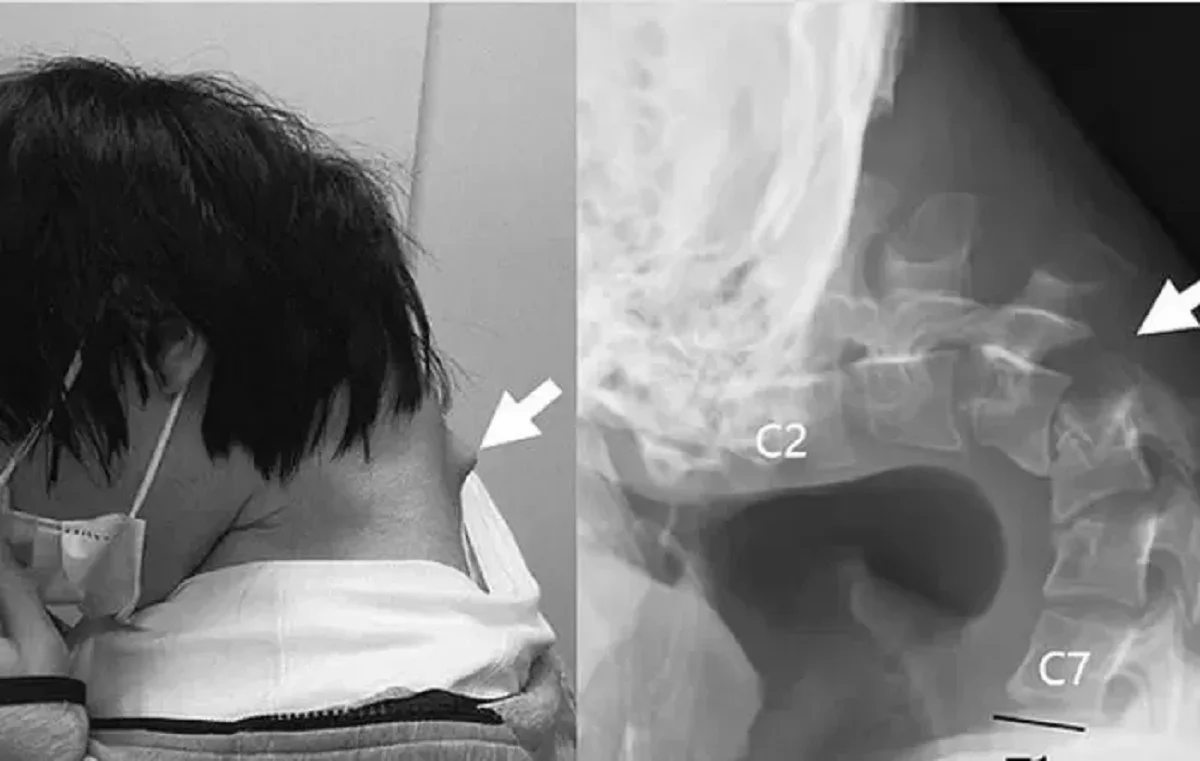

Жапонияда смартфонды шамадан тыс қолданған 25 жастағы жігітке сирек кездесетін «салбыраған бас синдромы» диагнозы қойылды. Бұл дерт көбіне жүйке-бұлшықет ауруларымен байланысты болғанымен, кей жағдайда ұзақ уақыт бойы бастың алға қарай еңкейіп тұруынан да туындауы мүмкін, деп хабарлайды Аlmaty.tv.

Daily Mail басылымының жазуынша, науқас күнделікті өмірінің басым бөлігін телефон экранына үңілумен өткізген. Соның салдарынан оның мойын омыртқасы деформацияға ұшырап, омыртқааралық тіндер зақымданған. Уақыт өте келе жігіттің мойын бұлшықеттері әлсіреп, басын көтеруге қауқарсыз болып қалған. Сонымен қатар тамақ жұтуда қиындықтар туындап, дене салмағын күрт жоғалта бастаған.

Дәрігерлер бастапқыда арнайы мойын тіреуіштерін қолданғанымен, нәтиже болмаған соң бірнеше кезеңнен тұратын күрделі ота жасады. Қисайып қалған омыртқа бөліктері мен зақымданған тіндер алынып, орнына темір таяныштар орнатылды. Алты айдан соң науқас басын қайта көтере алатын болған, сөйтіп омыртқасы жа қалпына келе бастаған. Бір жылдан кейін жағдайы тұрақты деп танылды.